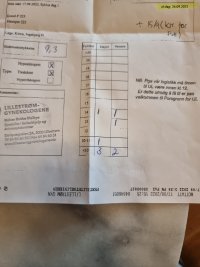

Uff... Jeg er veldig nedfor nå. Ferdig med kontrollen, og det er like få egg nå som ved kort protokoll.. Knakk sammen hos gynekologen, fordi jeg hadde virkelig håpet på ett bedre resultat. Satt der å gråt over resultatet.. Er ikke poenget med lang protokoll at det skal vokse likt? Jeg hadde 2 folikler på 14mm, 1 på 13mm, 1 på 10-11 mm og 5 på under 10. Jeg har så god amh, men likevel er foliklene smarsonme.

Vedlegg

Vis vedlegget 389232

Vis vedlegget 389232